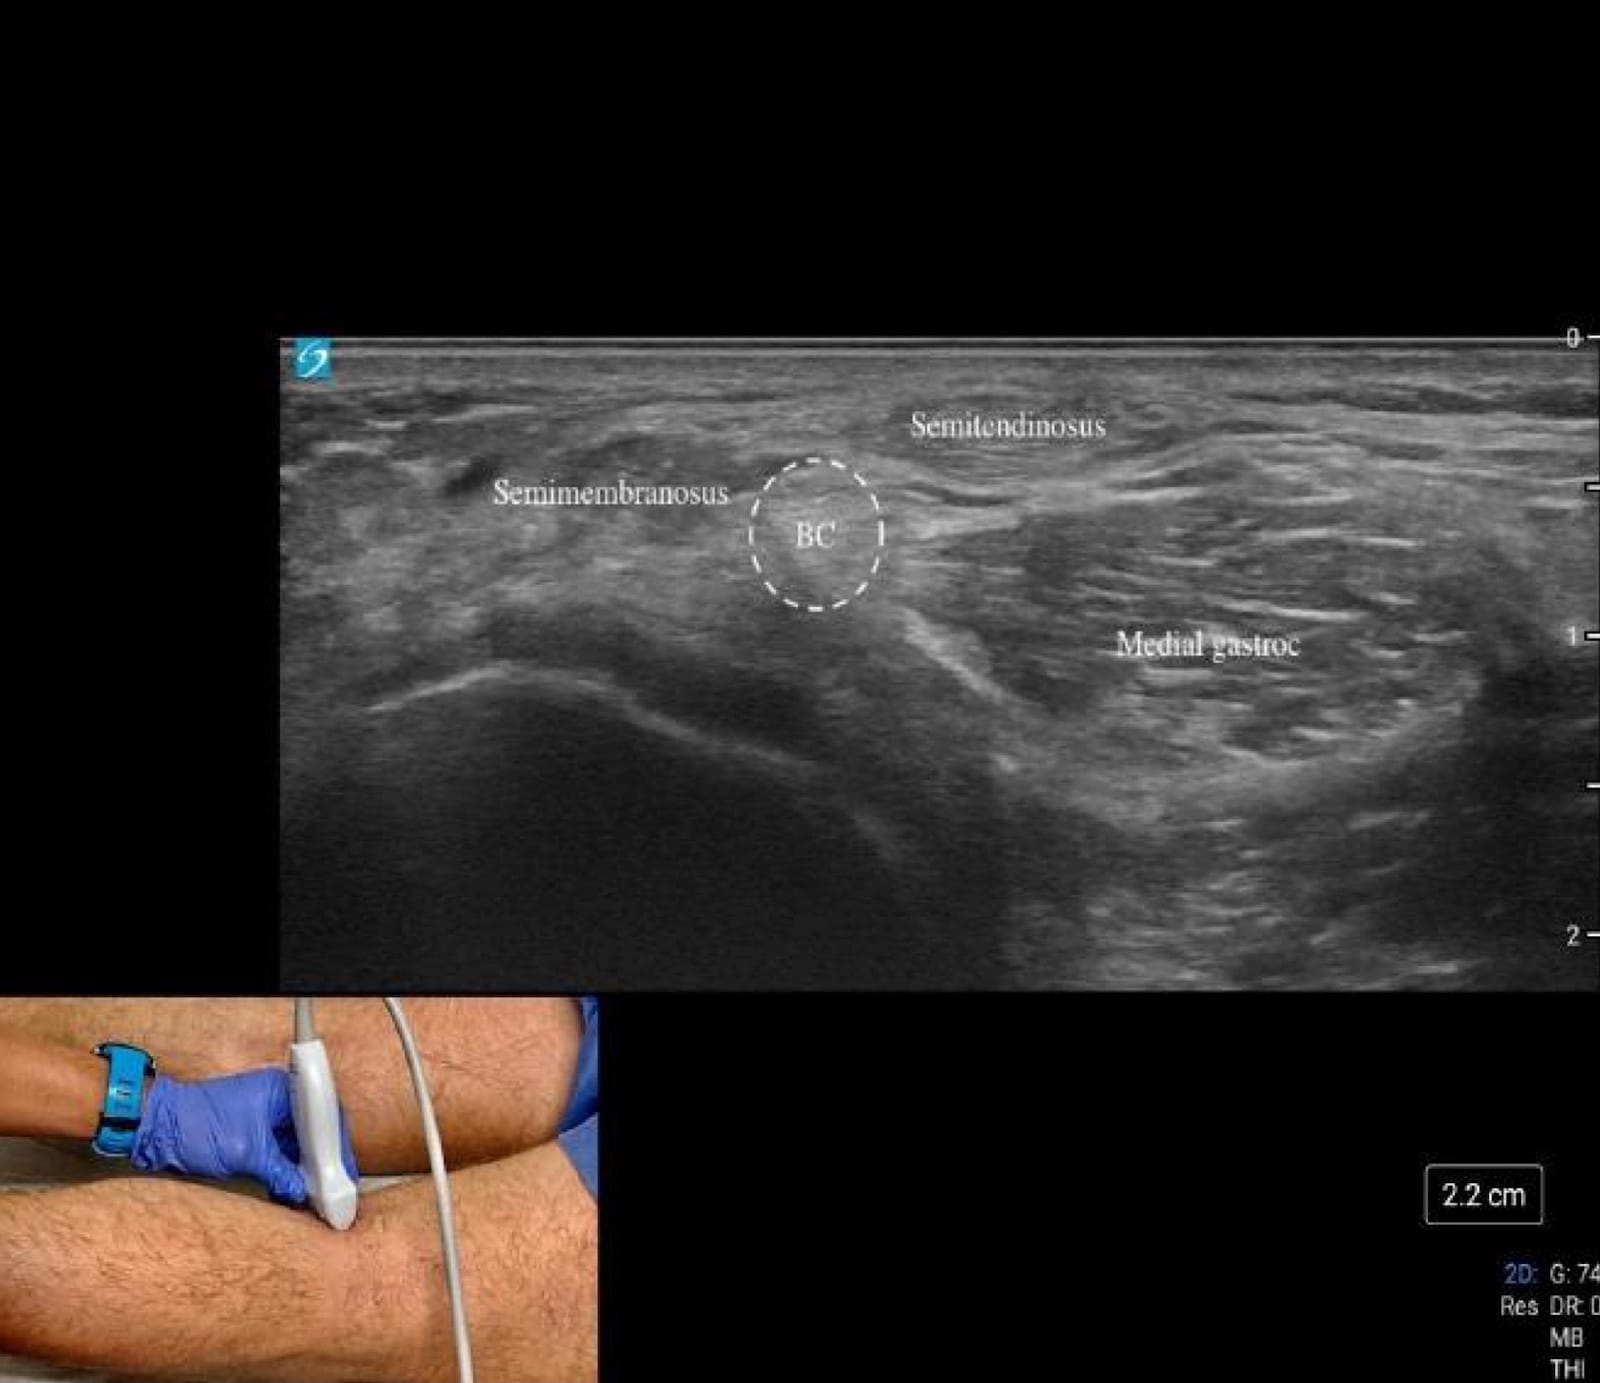

Begin at “home base” by palpating the semitendinosus tendon, felt as the medial string-like tendon on the posterior thigh. From here, sweep laterally and tilt the transducer between the semimembranosus tendon and the medial head of the gastrocnemius (refer to figures 8B-C and figure 4); persistent hypoechogenicity in this interval represents fluid within a Baker’s cyst (refer to figure 8C).

Next, follow the semimembranosus tendon distally in short axis as it broadens toward its tibial insertion, being mindful that anisotropy is common due to the steep fiber angle. Rotate into the long axis to track the tendon onto its tibial attachment, identifying the tibia distally as a hyperechoic bony landmark and the femur proximally, where overlying femoral cartilage can be evaluated. This systematic sweep allows for rapid assessment of the posterior joint space, key tendons, potential fluid collections, and adjacent osseous structures in a single diagnostic sequence.

Key Structures: Semimembranosus tendon, medial/lateral gastrocnemius heads, popliteal fossa (Figures 8A-C).

Pathology

- Baker’s cyst – anechoic/complex fluid collection between semimembranosus and medial gastrocnemius, often communicating with the joint (Figure 4C).